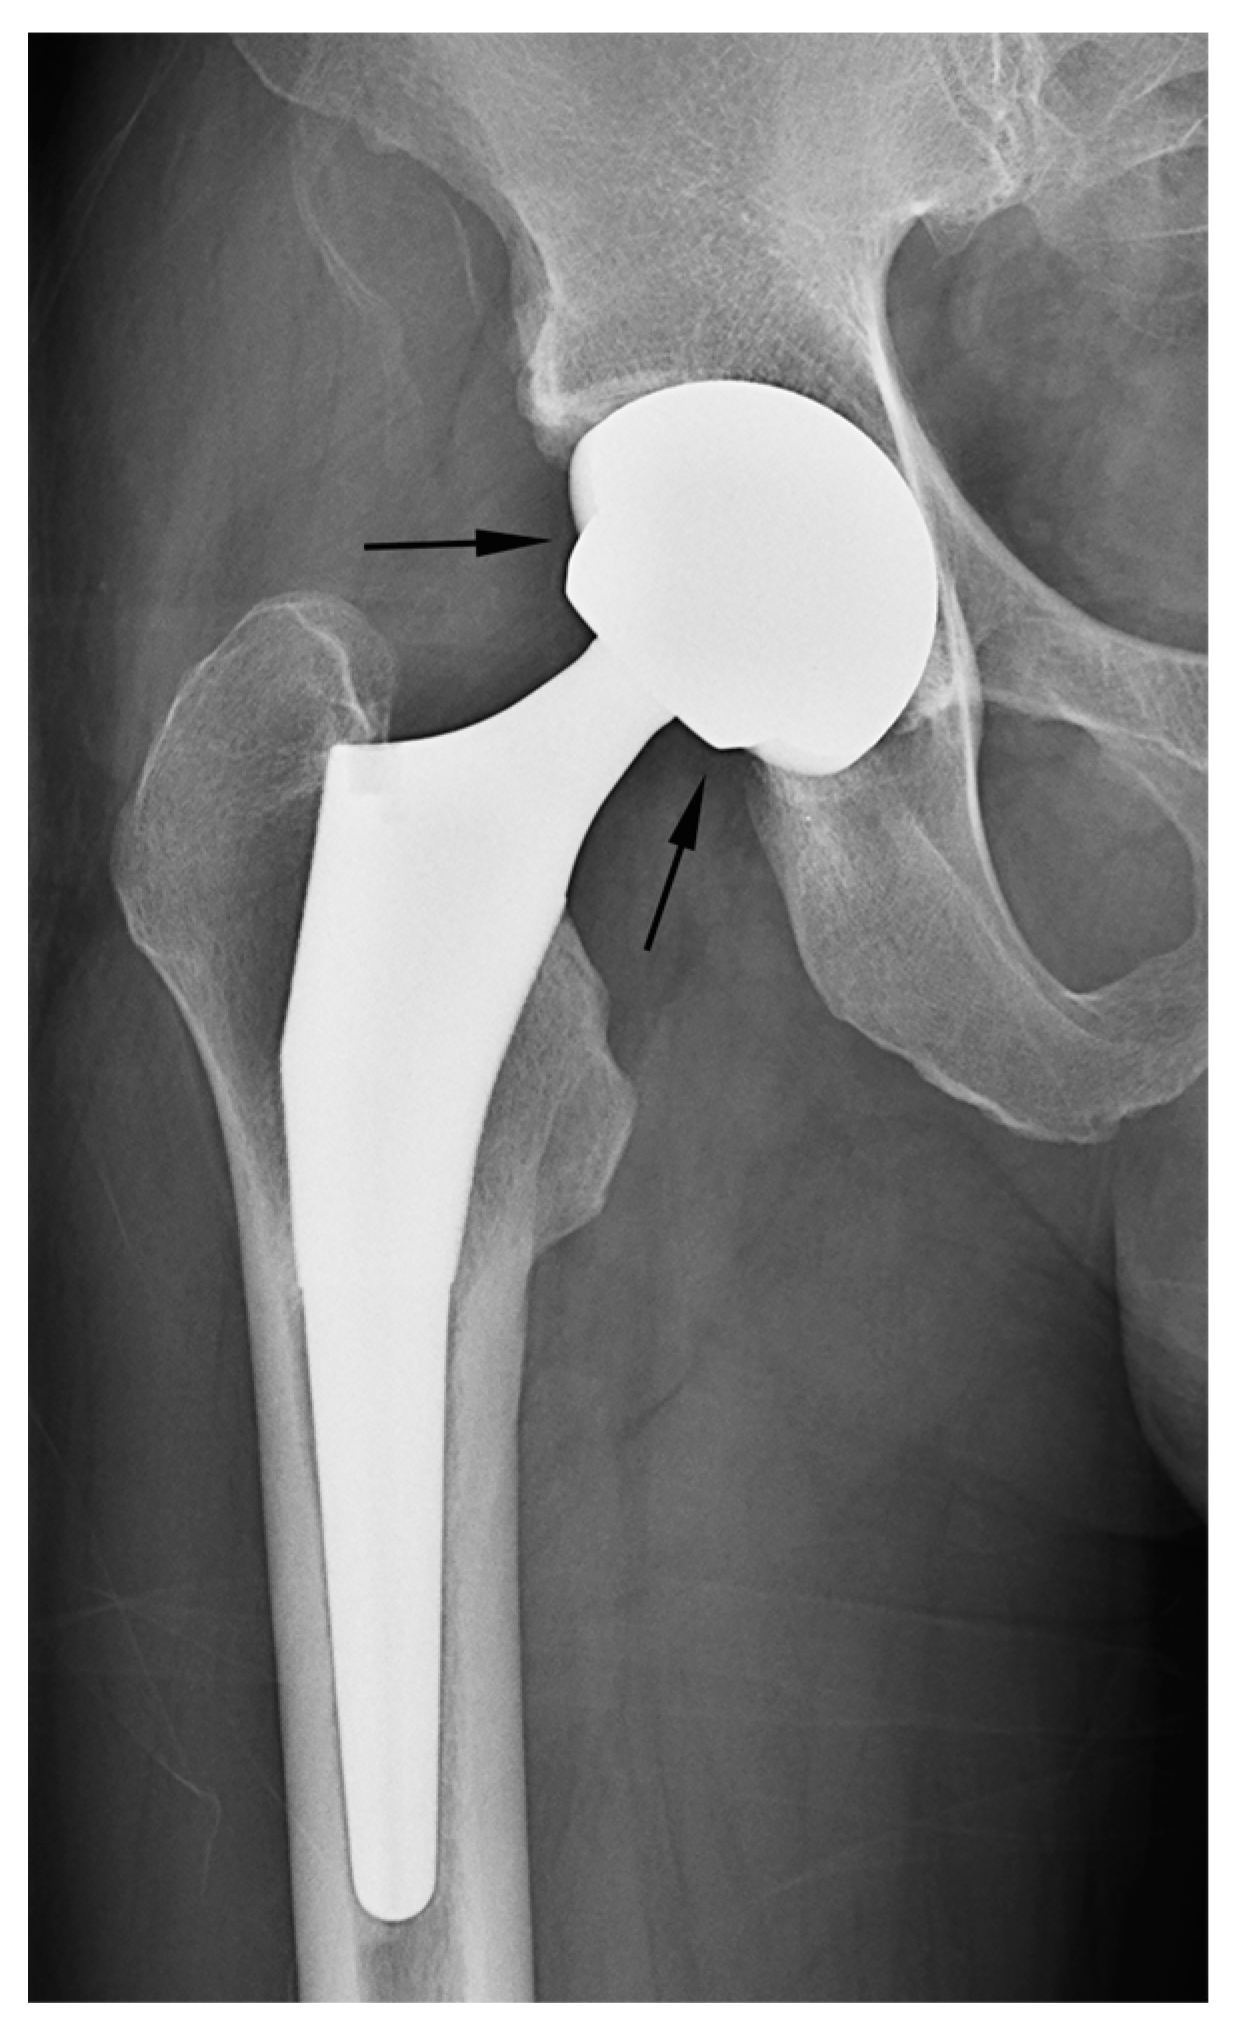

Figure 6.

Misinterpreted cases of acetabular sparing. (a) A simple radiograph after hemiarthroplasty showing the absence of the subchondral bone endplate and cartilage space (acetabular erosion of the bipolar cup) (arrows). When the presence of the adjacent cartilage joint space was used as the discriminator, the case was misinterpreted as THA by all readers. (b) Simple radiography after THA showing the preserved joint space and a subchondral bone plate of the acetabulum (arrow). When the presence of the adjacent cartilage joint space was used as the discriminator, two readers misinterpreted the case as a hemiarthroplasty.